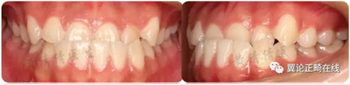

一個(gè)恒牙列早期的骨性3類(lèi)小女生,沒(méi)有顯著家族遺傳史。

磨牙尖牙均為近中關(guān)系,前牙反覆頜較深,下切牙舌傾代償(IMPA=88.8度)。下頜可以功能性后退至切對(duì)切。

從軟組織面型上看,患者面中份發(fā)育尚可,面下1/3發(fā)育過(guò)度。下唇外翻明顯。

治療后咬合狀態(tài)、側(cè)貌、以及微笑弧等都得到很大改善。